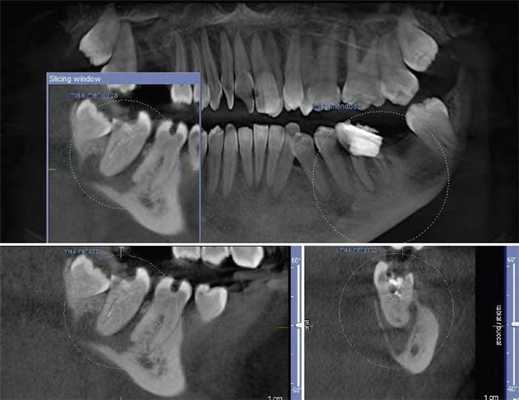

На томограммах и реконструктивных снимках было установлено, что 4.6, 4.7 зубы имеют особенность микроанатомии каналов. Мезиальные корни содержали по 2 канала, которые открывались отдельными апикальными отверстиями. В дистальных корнях обнаружили по 3 канала, которые сливались в одно апикальное отверстие. Причем третий (дистально-язычный) канал 4.7 зуба заканчивался на язычной стенке корня на уровне его середины (рис. 2) .

Рис. 2. КЛКТ. Аксиальные последовательные срезы 4.6, 4.7 зубов.

Параллельно с этим на КТ была выявлена несостоятельность реставрации 4.6 зуба. Пациентке было рекомендовано провести его лечение. Однако она обратилась в клинику только через полгода с острой болью в области 4.6 зуба. После клинического обследования и анализа особенностей строения канально-корневой системы 4.6 зуба на КЛКТ (рис. 7) было проведено эндодонтическое лечение 5-канального нижнего правого первого моляра по поводу необратимого симптоматического периодонтита 4.6 зуба.

Рис. 7. КЛКТ, МПР. Прицельная визуализация дистального корня 4.6 зуба.